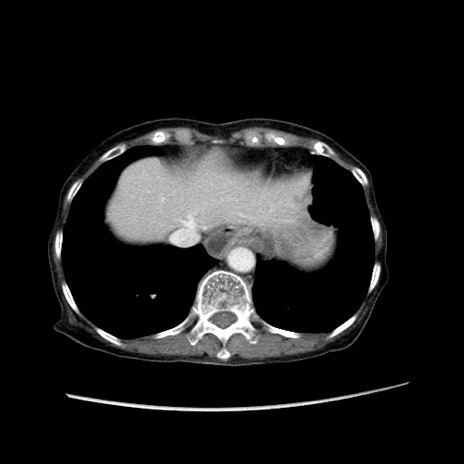

症例25(横断像)

【症例】80歳代女性

【主訴】胸のつかえ感

【現病歴】約9時間前に食後から胸のつかえた感じあり、嘔吐あり、来院。

【既往歴】胃癌(全摘)、胆摘、虫垂炎

【身体所見】心窩部に圧痛あり、反跳痛なし。

【データ】WBC 5700、CRP 0.05